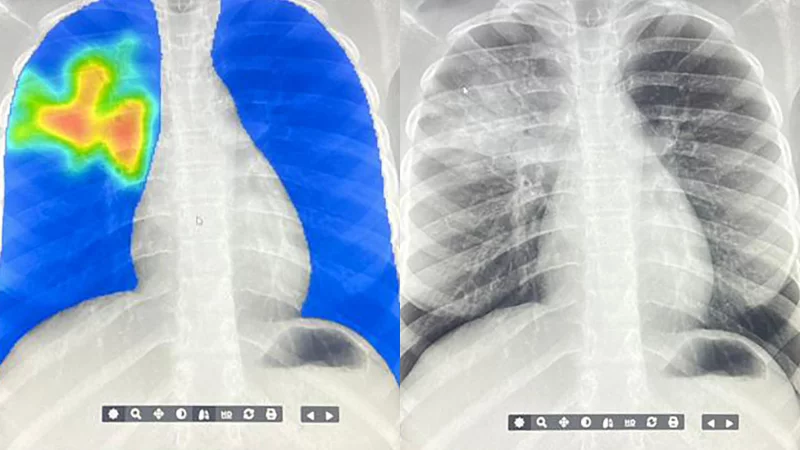

در بسیاری از کشورهای کمدرآمد و با درآمد متوسط، فناوری هوش مصنوعی اکنون در صف مقدم مبارزه با بیماری سل (TB) قرار گرفته است. این فناوری با تحلیل تصاویر اشعه ایکس و تولید نقشههای حرارتی که نواحی مشکوک به عفونت را با رنگهای زرد و قرمز نشان میدهد، به سرعت موارد ابتلا را شناسایی میکند.

در مالی، اپراتورهایی که پزشک نیستند اما آموزش دیدهاند، تصاویر اشعه ایکس را گرفته و به کمک نرمافزارهای هوش مصنوعی تفسیر میکنند. اگر بخشهایی از ریه در تصویر قرمز رنگ شود، نمونه خلط برای تأیید نهایی به آزمایشگاه فرستاده میشود. این روش نهتنها زمان تشخیص را کاهش داده بلکه نیاز به جمعآوری نمونههای خلط را تقریباً به نصف رسانده است.